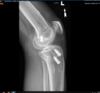

X-rays were reviewed and is most notable for previous ACL reconstruction with appropriate tibial tunnel and a previous metal interference screw, and it to my interpretation is a vertical femoral tunnel with cortical fixation device, no significant radiographic evidence of tunnel osteolysis or hardware failure.

I also was able to better interpret the tunnel placement as well as absence of any tunnel osteolysis.